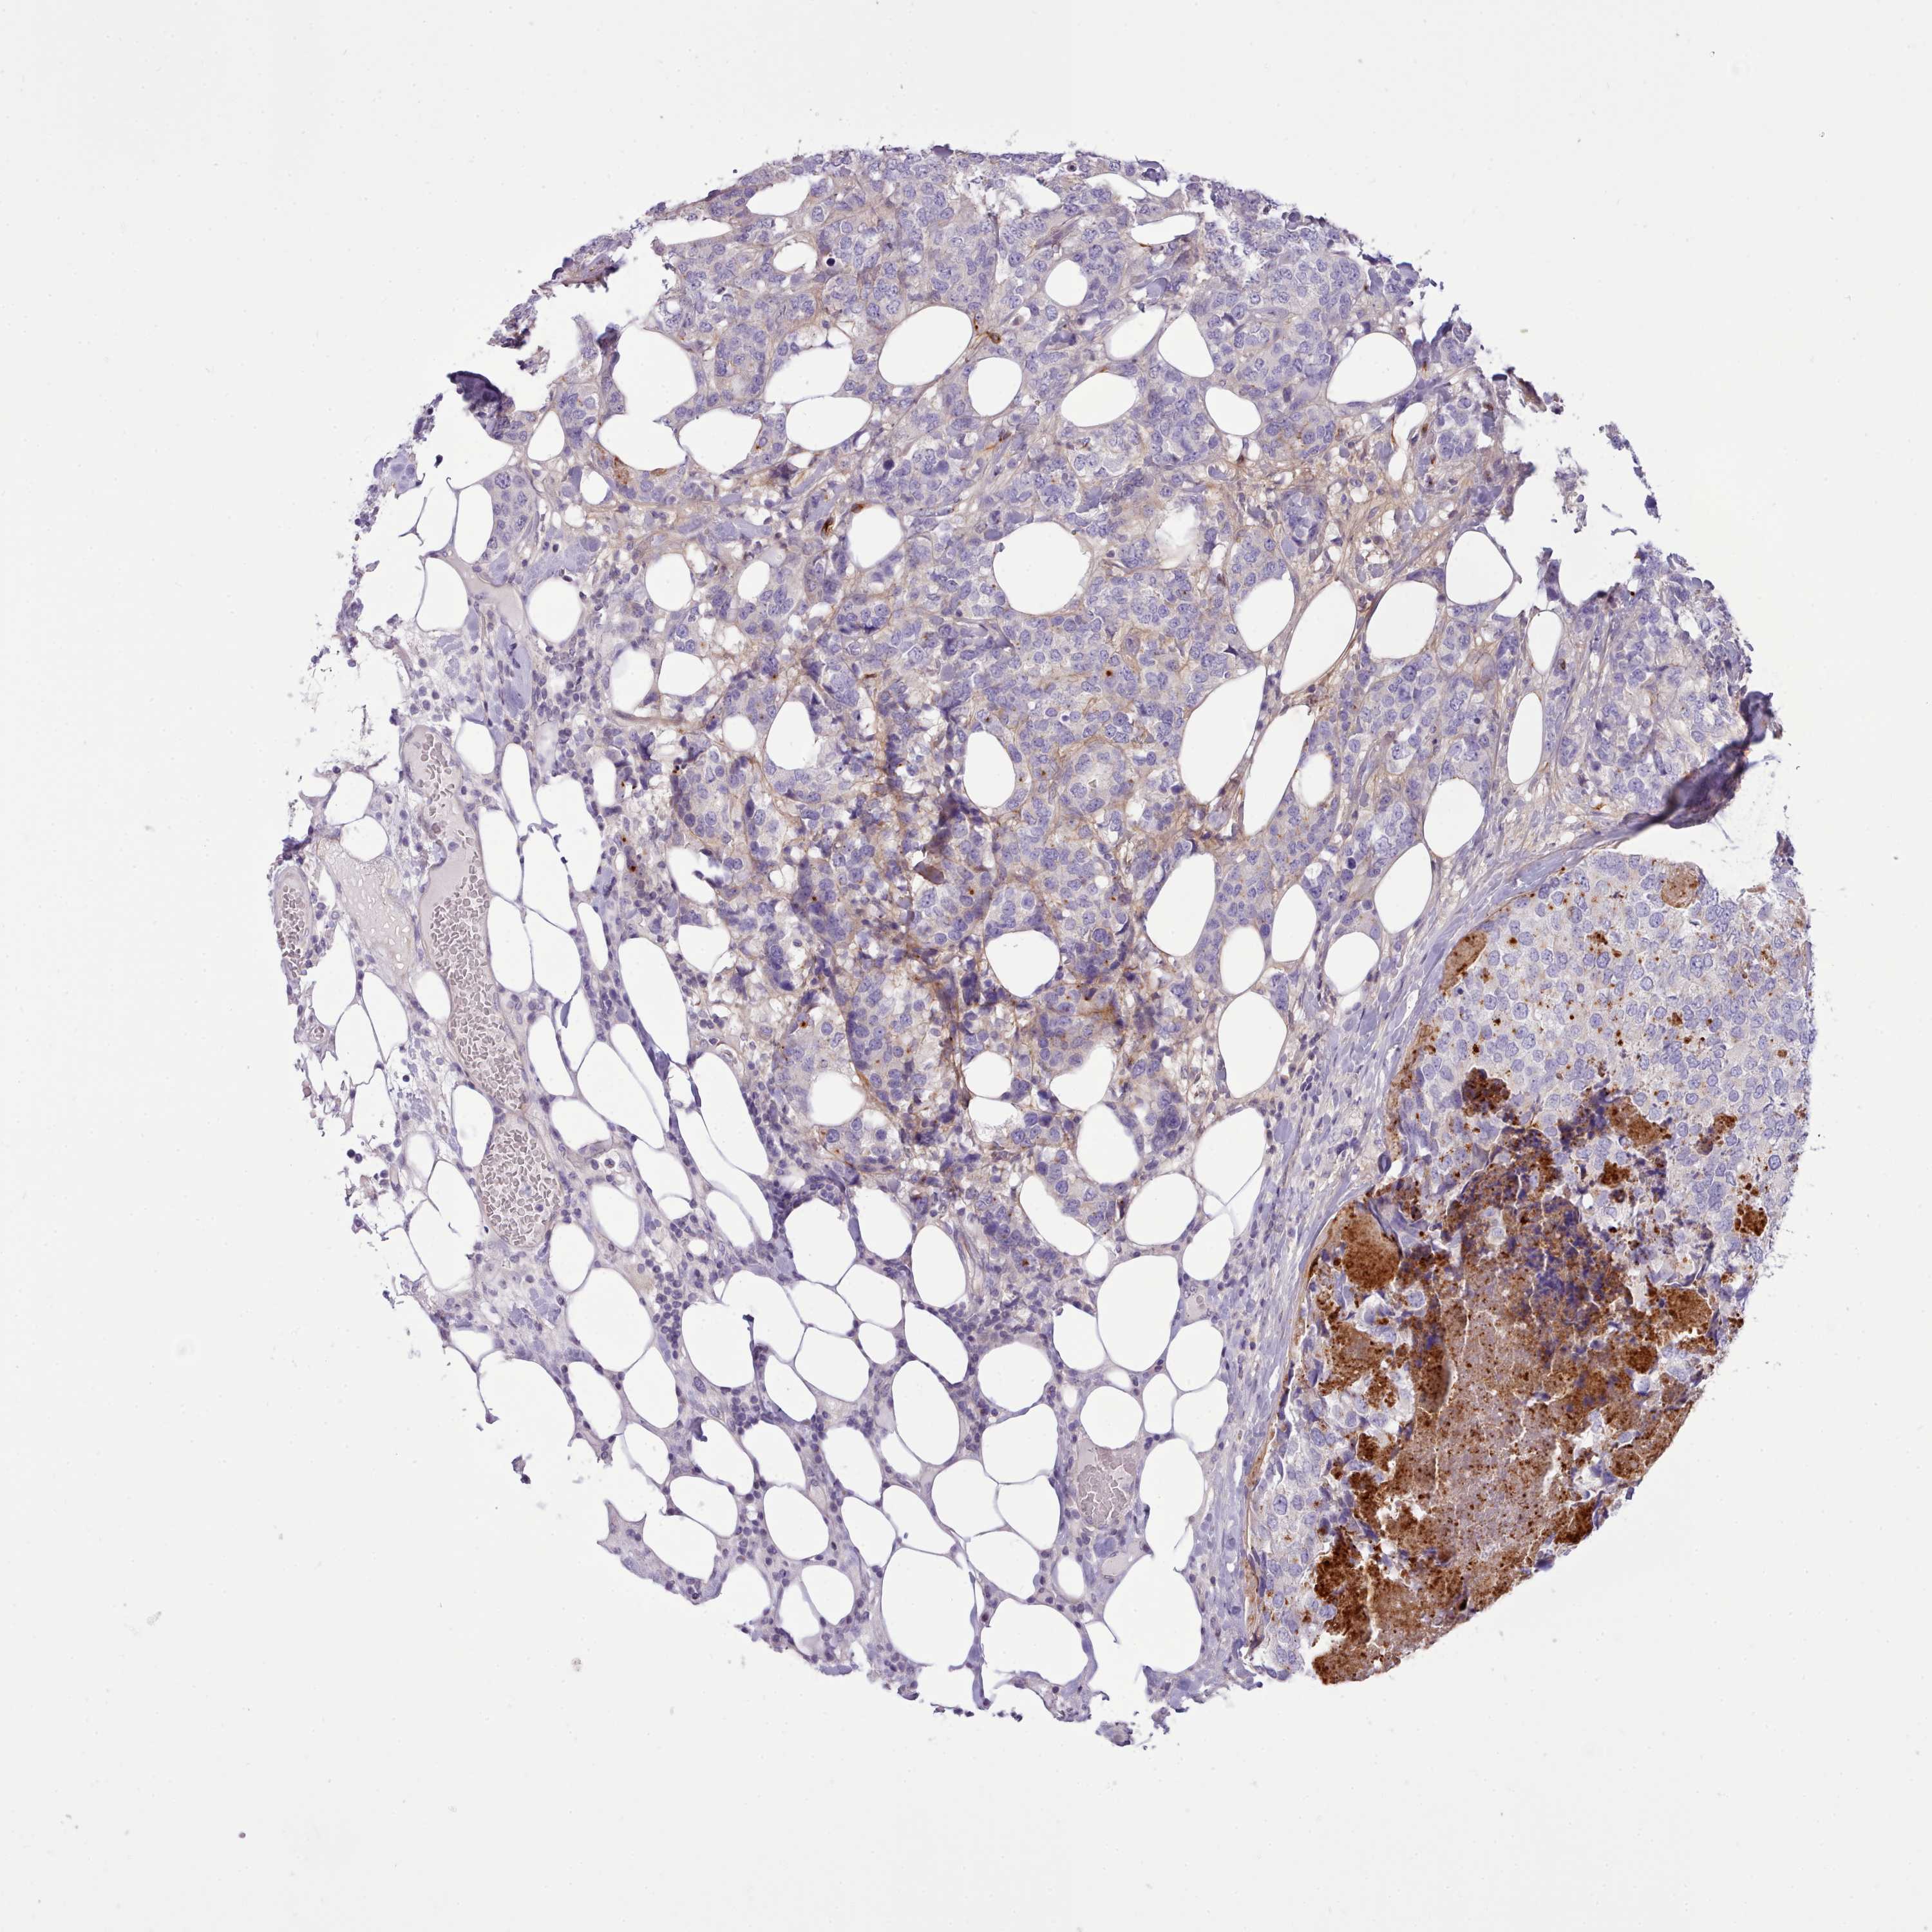

BRCA TCGA BRCA VALIDATION PROTEIN EXPRESSION

ANTIBODIES

AND

VALIDATION